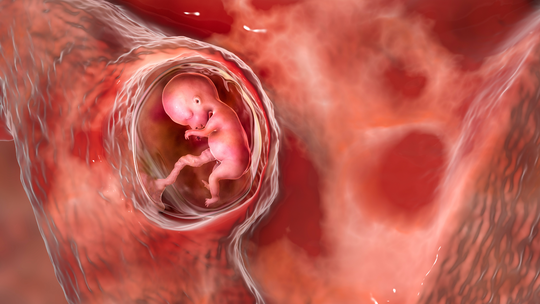

"Common Causes of Miscarriage in Early Pregnancy: What You Should Know\",\"imageid\":\"131009054\",\"imgsize\":\"1661384\",\"lu\":\"May 12, 2026, 02:25 PM\",\"id\":131009054,\"dl\":\"May 11, 2026, 03:00 PM\",\"seolocation\":\"pregnancy/causes-of-miscarriage-in-early-pregnancy\",\"subsecname\":\"Pregnancy\",\"subsecmsid\":112886004,\"syn\":\"It is very natural to experience happiness and a little anxiety simultaneously during the early weeks of pregnancy. Concerns about miscarriage are common, and many causes are not within your control. Learning about these can help you feel more supported.\",\"agency\":{\"id\":87654322},\"tn\":\"news\",\"imgratio\":\"0.5625\",\"dm\":\"t\",\"subsecseolocation\":\"pregnancy\",\"host\":\"prega\",\"slot\":\"10\"},{\"hl\":\"How Often Should You Bathe a Newborn Baby?\",\"imageid\":\"131005010\",\"imgsize\":\"35408\",\"lu\":\"May 11, 2026, 01:00 PM\",\"id\":131005010,\"dl\":\"May 11, 2026, 01:00 PM\",\"seolocation\":\"baby/bathing-newborn-baby-how-often-should-you-do-it\",\"subsecname\":\"Baby\",\"subsecmsid\":113631885,\"syn\":\"Bathing your newborn can feel both special and a little overwhelming, especially if you are unsure how often to bathe them. Fortunately, newborns do not require everyday bathing. You can take care of your baby's sensitive skin, make bathing time a peaceful experience, and create a bonding experience by knowing the proper frequency and using safe, gentle bathing techniques.\",\"agency\":{\"id\":87654322},\"tn\":\"news\",\"imgratio\":\"0.5625\",\"dm\":\"t\",\"subsecseolocation\":\"baby\",\"host\":\"prega\",\"slot\":\"11\"},{\"hl\":\"Blood Clots During Pregnancy: Understanding the Risks and Complications\",\"imageid\":\"131002969\",\"imgsize\":\"1495735\",\"lu\":\"May 11, 2026, 11:00 AM\",\"id\":131002969,\"dl\":\"May 11, 2026, 11:00 AM\",\"seolocation\":\"pregnancy/blood-clots-during-pregnancy-risks-symptoms-prevention\",\"subsecname\":\"Pregnancy\",\"subsecmsid\":112886004,\"syn\":\"Blood clots during pregnancy are a serious matter, but the positive part is that they are uncommon and usually preventable with proper awareness and care. Many expectant parents worry about this issue because pregnancy naturally changes how the blood behaves. But understanding the facts helps you stay safe and enjoy this special time.\",\"agency\":{\"id\":87654322},\"tn\":\"news\",\"imgratio\":\"0.5625\",\"dm\":\"t\",\"subsecseolocation\":\"pregnancy\",\"host\":\"prega\",\"slot\":\"12\"},{\"hl\":\"IVF Complications: What Every Couple Should Prepare For\",\"imageid\":\"130957503\",\"imgsize\":\"1771006\",\"lu\":\"May 11, 2026, 09:00 AM\",\"id\":130957503,\"dl\":\"May 11, 2026, 09:00 AM\",\"seolocation\":\"getting-pregnant/ivf-complications-symptoms-and-risks\",\"subsecname\":\"Getting Pregnant\",\"subsecmsid\":112886008,\"syn\":\"In vitro fertilisation (IVF) offers real hope to many couples facing infertility challenges. While the procedure has become much safer over the years, it still carries certain risks and possible complications. Understanding these helps you prepare better and stay alert during the journey.\",\"agency\":{\"id\":87654322},\"tn\":\"news\",\"imgratio\":\"0.5625\",\"dm\":\"t\",\"subsecseolocation\":\"getting-pregnant\",\"host\":\"prega\",\"slot\":\"13\"},{\"hl\":\"Cervical Incompetence: The Silent Cause of Second Trimester Loss\",\"imageid\":\"130956971\",\"imgsize\":\"1233562\",\"lu\":\"May 08, 2026, 07:00 PM\",\"id\":130956971,\"dl\":\"May 08, 2026, 07:00 PM\",\"seolocation\":\"pregnancy/cervical-incompetence-second-trimester-loss\",\"subsecname\":\"Pregnancy\",\"subsecmsid\":112886004,\"syn\":\"For many women, this is their first encounter with a condition called cervical incompetence, and tragically, it often announces itself only after a loss. This walks you through what it is, why it happens silently, how it's diagnosed, and what treatments and monitoring options exist to protect your next pregnancy.\",\"agency\":{\"id\":87654322},\"tn\":\"news\",\"imgratio\":\"0.5625\",\"dm\":\"t\",\"subsecseolocation\":\"pregnancy\",\"host\":\"prega\",\"slot\":\"14\"},{\"hl\":\"Can You Plan a Pregnancy After Recovering From Cancer?\",\"imageid\":\"130956443\",\"imgsize\":\"1165295\",\"lu\":\"May 08, 2026, 05:00 PM\",\"id\":130956443,\"dl\":\"May 08, 2026, 05:00 PM\",\"seolocation\":\"getting-pregnant/pregnancy-planning-after-cancer-treatment\",\"subsecname\":\"Getting Pregnant\",\"subsecmsid\":112886008,\"syn\":\"Planning pregnancy after cancer recovery is possible for many individuals with proper medical guidance. Learn about fertility considerations, safe timing, and expert recommendations to help you make informed, confident decisions about stepping into parenthood.\",\"agency\":{\"id\":87654322},\"tn\":\"news\",\"imgratio\":\"0.5625\",\"dm\":\"t\",\"subsecseolocation\":\"getting-pregnant\",\"host\":\"prega\",\"slot\":\"15\"}]}]}]]\n"])